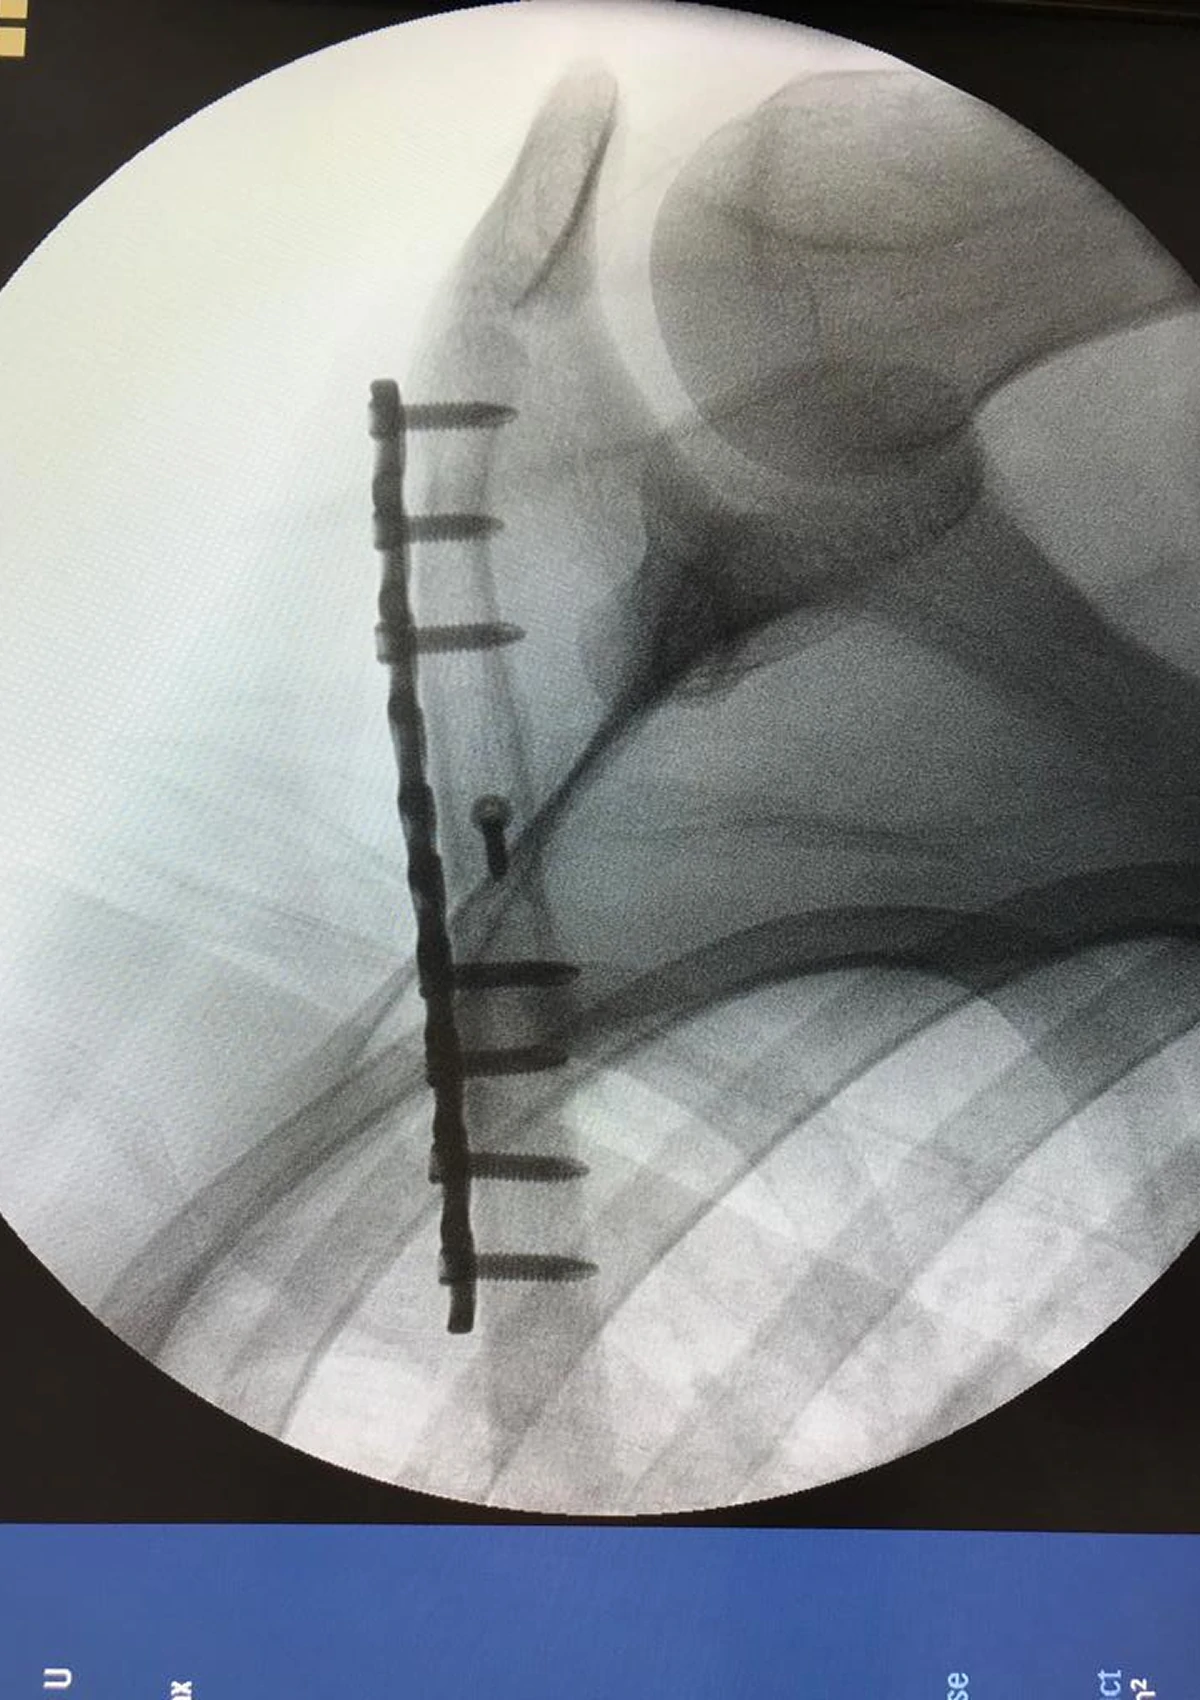

Before & After